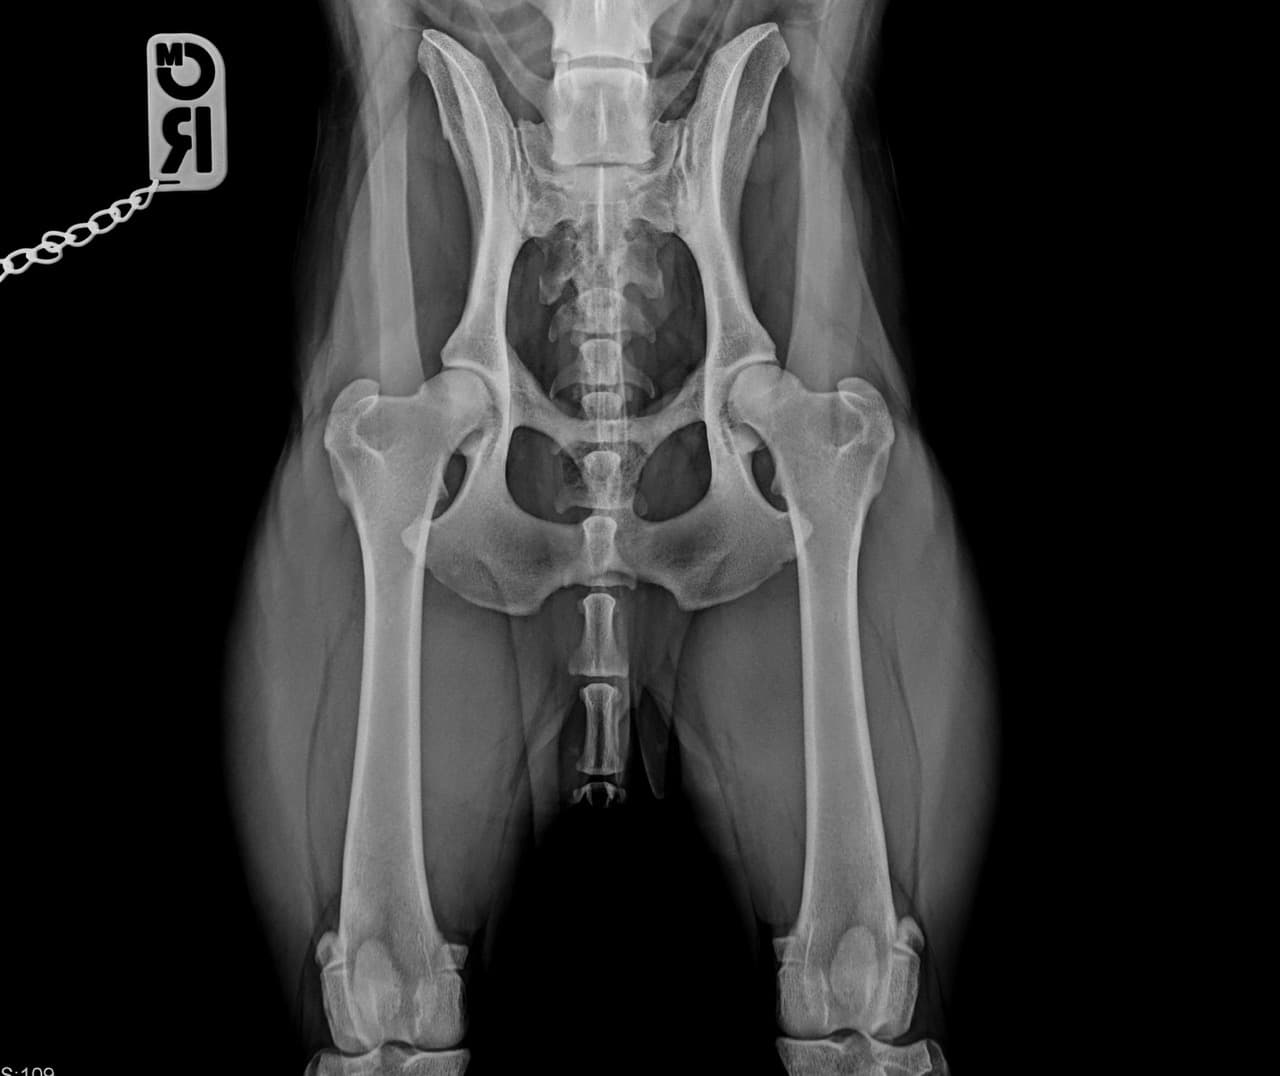

- Zuchtuntersuchung (HD und ED-Röntgen, Patella-Lux)

Bildgebende Untersuchung

- Digitales Röntgen (DR-System)

- Knochenchirurgie (Osteosynthesen, Frakturversorgung)

- Gelenkchirurgie (Kreuzbandriss: TTA Tight Rope, lateraler Fadenzügel) (Patella Lux: Ridge Stop, Transposition Tuberositas tibiae auch kombiniert mit TTA) Hüftgelenksluxation